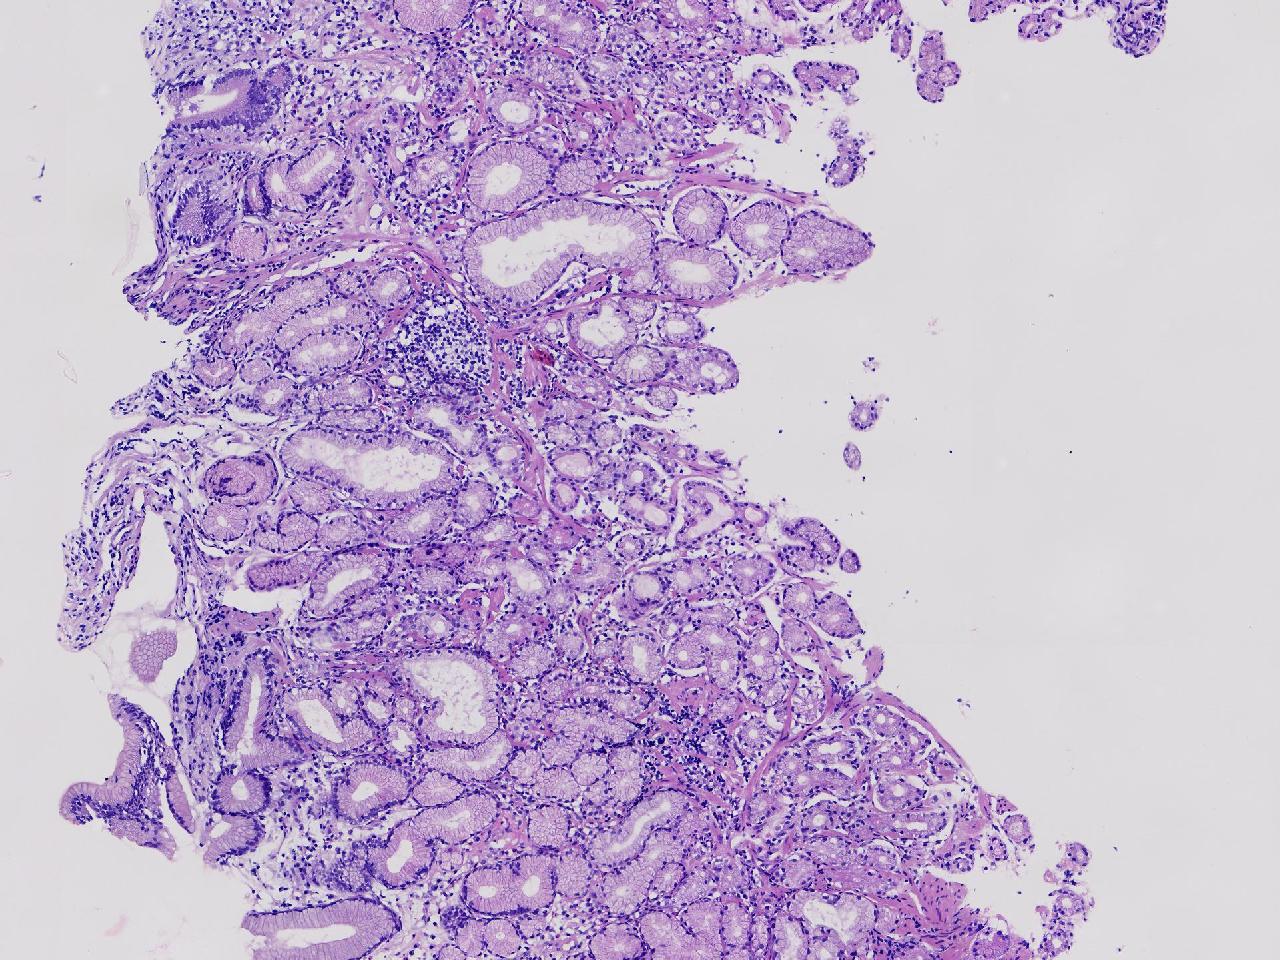

男,76岁。胃体前壁见1纵行溃疡,底覆白苔,周围粘膜充血水肿,于病变周边取材3块。

胃体前壁活检

灰白色不整形软组织3块,直径均0.2厘米。

图1

粘膜中度慢性炎伴糜烂,固有层淋巴细胞聚集